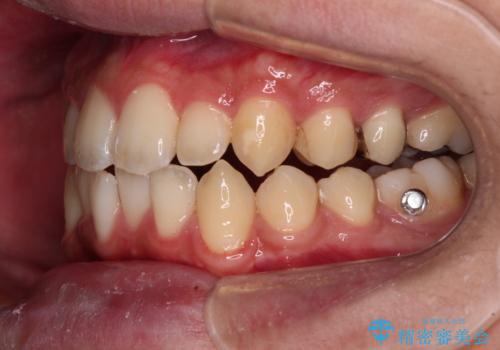

インビザライン特有の、治療後半に奥歯が咬み合わないという事象が長引きました。

咬み合わないときの対処方法は色々とありますが、ゴムかけなどを活用して噛めるようにしました。